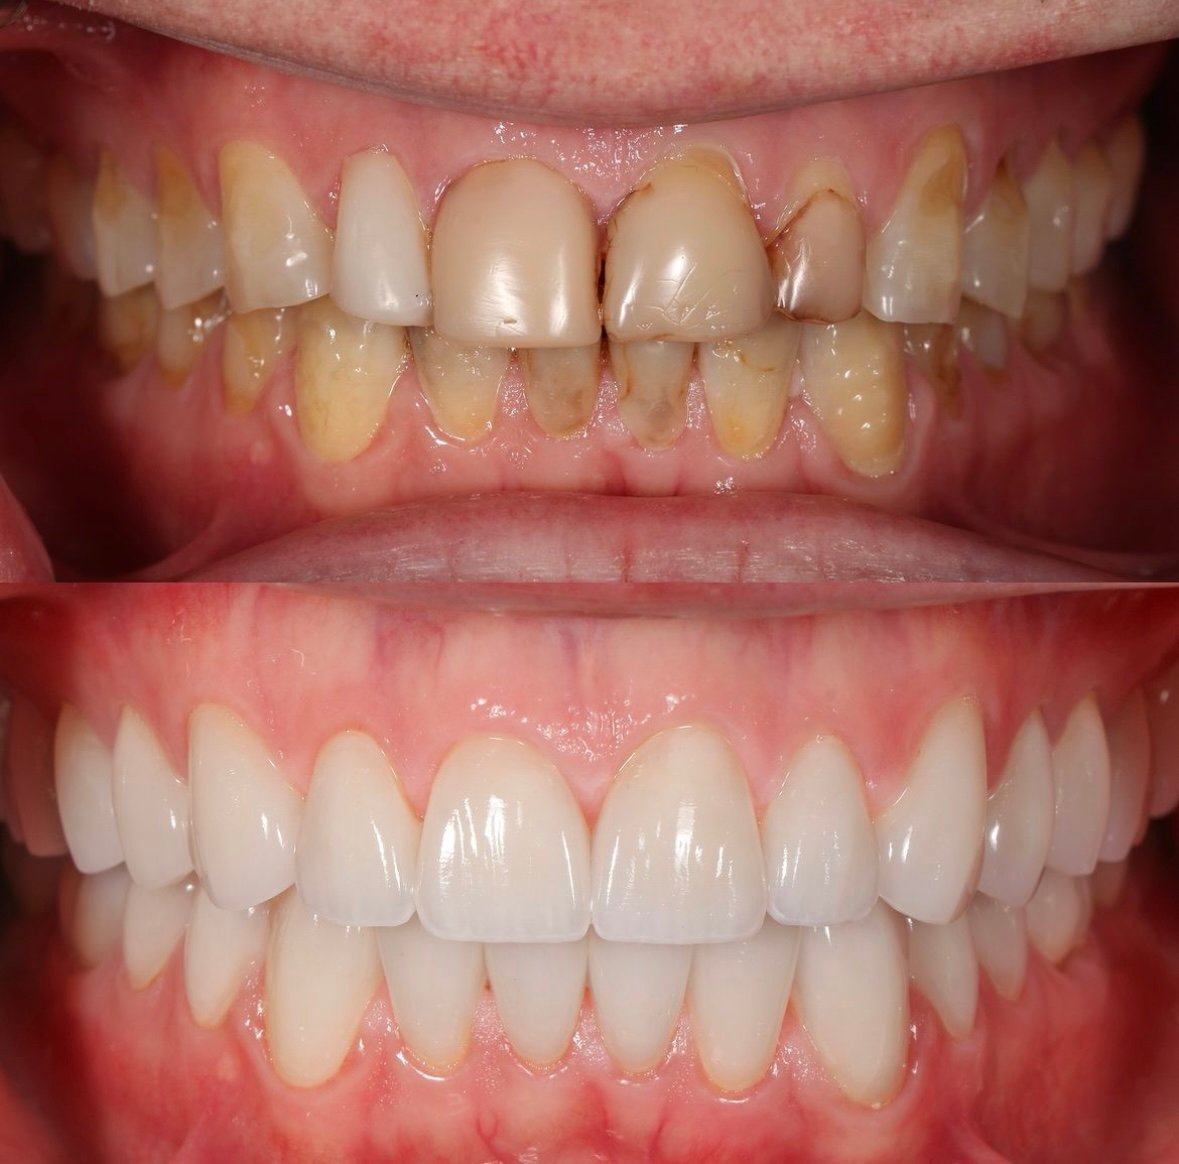

Lavori

Nuove idee

per un sorriso più sano